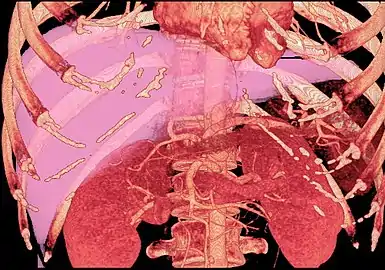

MDCT image. 3D image created by MDCT can clearly visualize the liver, measure the liver volume, and plan the dissection plane to facilitate the liver transplantation procedure.